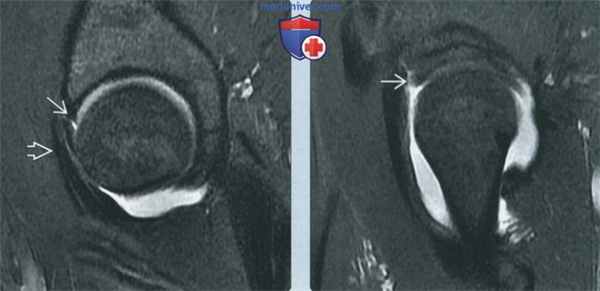

(Слева) МР-артрография в режиме Т1ВИ FS, аксиальный срез: выявляется подвздошно-поясничный импинджмент. В положении «на 3 часа» определяется неровный контур передней суставной губы, в толще которой отмечается контрастный препарат. Сухожилие подвздошно-поясничной мышцы в этом месте перекидывается через суставную губу и располагается спереди от нее.

(Справа) МР-артрография в режиме Т1ВИ FS, аксиальный срез, этот же пациент: в положении «на 1 час» суставная губа выглядит интактной. Подвздошно-поясничная мышца проходит кпереди от вертлужной впадины.

(Слева) МР-артрография в режиме PD FS, сагиттальный срез, этот же пациент: в положении «на 3 часа» визуализируется разрыв суставной губы. Спереди ее пересекает сухожилие подвздошно-поясничной мышцы.

(Справа) МР-артрография в режиме PD FS, сагиттальный срез, этот же пациент: отмечается, что верхняя часть суставной губы интактна. При ее разрыве следовало бы заподозрить скорее бедренно-вертлужный, чем подвздошно-поясничный импинджмент.